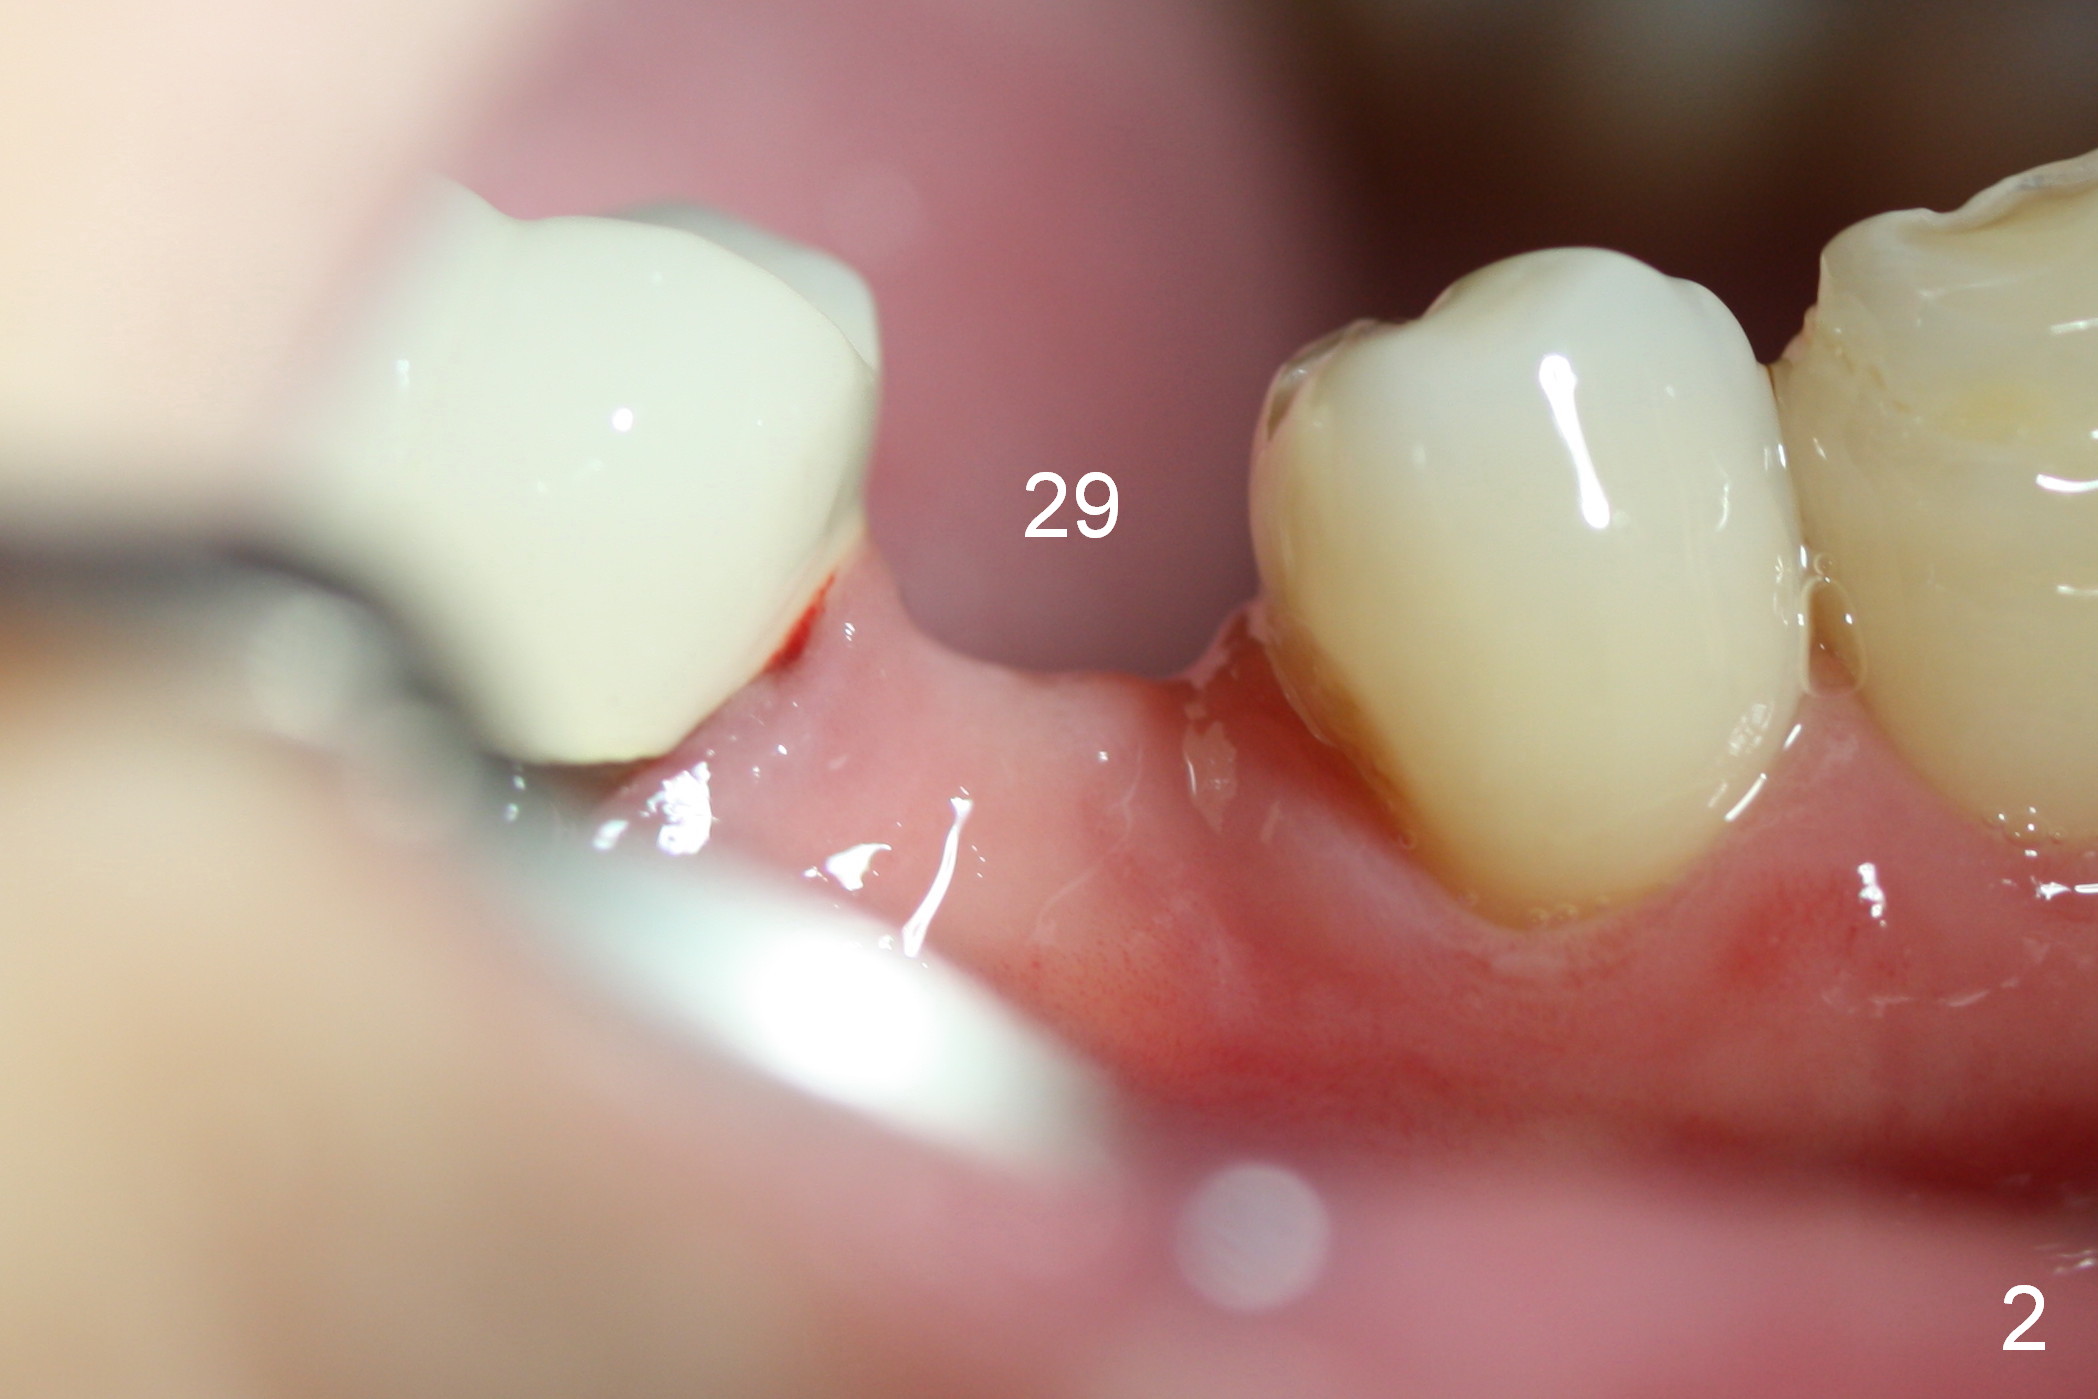

A 57-year-old woman will return for implant placement at #29, which has narrow space mesiodistally (Fig.1,2), buccolingually (Fig.3) and vertically (Fig.1, i.e., close to the Mental Loop (red outline)). Use a 2.5 or 3 mm tissue-punch from the 1-piece implant kit for access. After removal of the gingival tissue at the access, measure the tissue depth. To avoid complication associated with the narrow ridge, an incision approach appears more appropriate. The initial depth will be 12 mm using 1.2 mm drill and take PA.